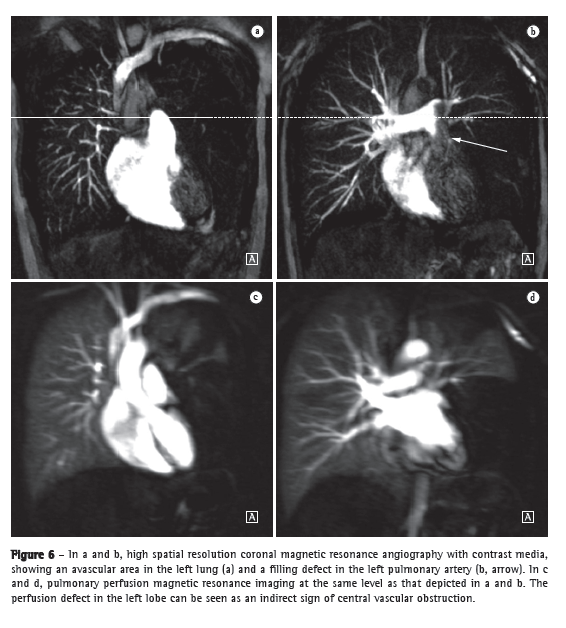

Substantial technical advances in pulmonary MRA have been introduced in recent years (Figures 5 and 6). Continued improvements are ongoing and include the use of parallel imaging, view sharing, time-resolved echo-shared angiography,(17-19) and pulmonary perfusion. These techniques have shortened MRA acquisition time, made it less susceptible to motion artifacts, and improved spatial resolution. One study showed that a combined magnetic resonance protocol (progressing from real-time MRI to perfusion MRI to MRA) is reliable and sensitive, producing results similar to those obtained with 16-slice multidetector CT.(18)

In 2003, Stein et al.(20) conducted a meta-analysis of the use of gadolinium-enhanced MRI for the depiction of acute pulmonary embolism. The authors used conventional pulmonary angiography as the reference standard. They found that the reported sensitivity of the procedure covered a broad range (77-100%) and that the reported specificity was uniformly high (95-98%).(20) In the most recent of the studies evaluated in that meta-analysis, Oudkerk et al.(21) showed that the sensitivity of contrast-enhanced MRI for pulmonary embolism was 100% in the central and lobar arteries; 84% in the segmental arteries; and only 40% in the subsegmental branches.

In cases of suspected acute pulmonary embolism, MRI with a state-of-the-art, three-component protocol (true fast imaging with steady-state precession; perfusion; and MRA with parallel acquisition) has recently been shown to be highly accurate.(18) The reported per-patient sensitivity and specificity, respectively, are 85% and 98% for the true fast imaging sequence; 100% and 91% for the perfusion sequence; and 77% and 100% for the MRA. The combined protocol has a reported sensitivity of 100% and a reported specificity of 93%. Although MRI and MRA are specific, they have low sensitivity, particularly for subsegmental pulmonary embolism. Overall, the combined MRI protocol has been found to be more reliable and sensitive than is 16-slice multidetector CT.(18) The average MRI examination time is reported to be approximately 10 min.(18)

The use of MRI allows the comprehensive assessment of pulmonary hypertension, MRA and perfusion sequences making it possible to identify and differentiate between pulmonary embolism and other disease entities.(22,23) In addition, MRA allows for an in-depth evaluation of the location of the thromboembolic material, and, for surgical planning, MRA is equally as useful as are digital subtraction angiography and CT angiography.(24,25) In MRI, perfusion sequences can be quantitatively evaluated, allowing the severity of small-vessel disease to be assessed. The reduction in perfusion correlates with disease severity, and preliminary results suggest that perfusion is a sensitive surrogate for disease monitoring.(4) Structural imaging of the lung will allow the exclusion of parenchymal diseases. Measurements of blood flow and right heart pressures allow pulmonary arterial pressure and cardiac strain to be estimated, as well as facilitating the identification of concomitant valvular disease.